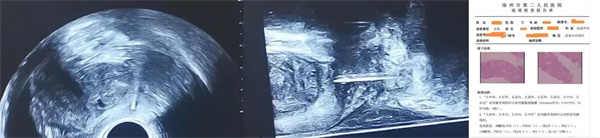

不久前,一名60来岁的男性患者因"发现前列腺特异抗原(PSA)增高半月"入住我院。检查显示,其总PSA测定值高达91.000ng/ ml,游离PSA测定值为17.620ng/mL ,游离/总前列腺特异抗原比值为0.19。患者平素身体健康,无其他异常既往史,入院后,磁共振及经直肠双平面超声均提示外周带存在可疑结节。随后,在我院行经直肠会阴路径前列腺穿刺,病理检查明确诊断为前列腺腺泡腺癌。依托精准的前期诊断,该患者在我院顺利行前列腺癌根治手术,现恢复良好,每一次成功的案例都是该技术临床优势的有力体现。

经直肠双平面超声技术,同时配备横断面和纵断面两个探头,能够获取前列腺的立体图像,清晰呈现前列腺的各个区域,就连传统单平面超声难以显示的尖部和前部也能清晰呈现,显著提升了穿刺的精准度。手术全程约30分钟,病人可自主选择在全麻或局麻下进行。

双平面超声可以同时显示针道的全程及前列腺的全貌,对针和穿刺目标更好的把控,可实现更精准的定位组织取材满意度高,提高穿刺阳性率,减少漏诊。